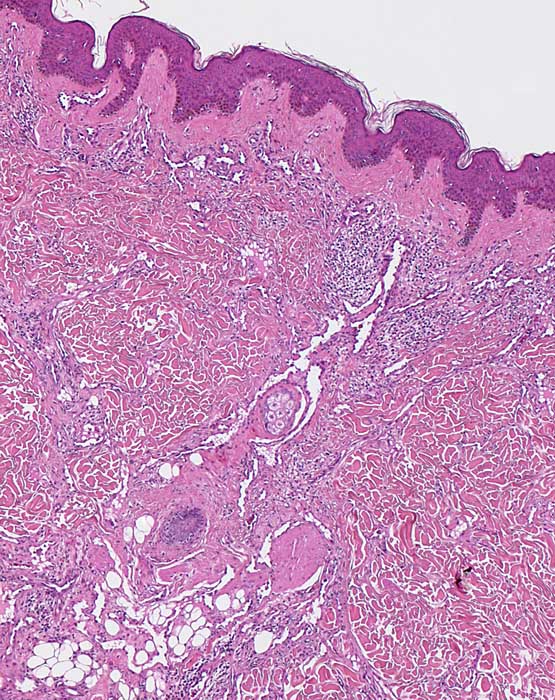

PathoPic – image database / PathoPic ID 7377 - Kaposi Sarkom Patch Stadium

Kaposi Sarkom Patch Stadium

Haut, untere Extremität

Irreguläre, von hyperchromatischen Endothelien gesäumte Spalten in unmittelbarer Nachbarschaft zu den oberen Plexusgefässen und fleckförmiges lymphoplasmazelluläres Infiltrat. Die Spalten sind bevorzugt um Hautadnexe angeordnet ( Promontorium Zeichen). und enthalten teilweise Erythrozyten. Die papilläre Dermis ist weitgehend ausgespart von atypischen Gefässproliferaten.

Hellrote Flecken an den unteren Extremitäten.

Histologie

50